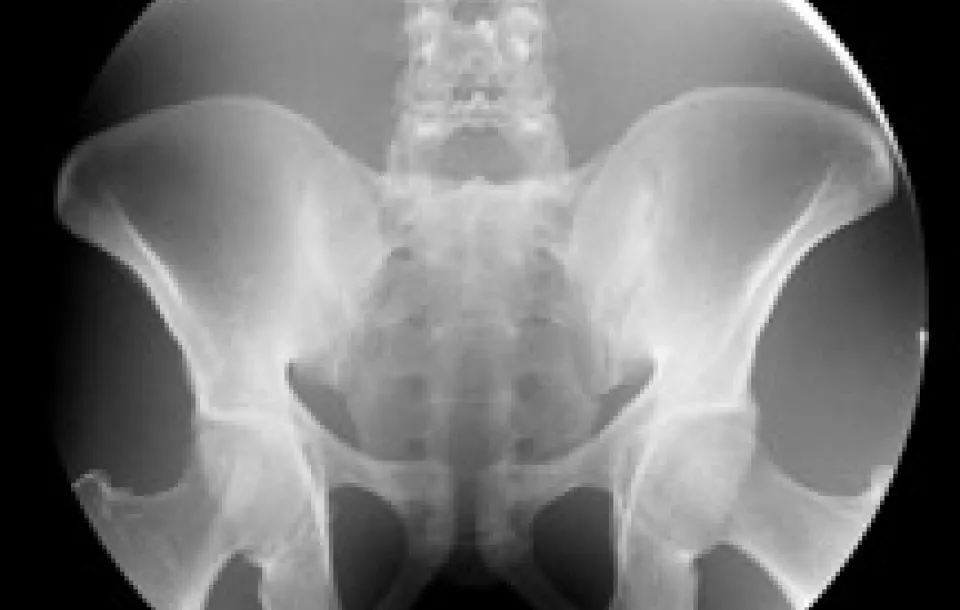

This fluoroscopy training and testing workshop provides an in-depth review of state-of-the-art fluoroscopic equipment technology and appropriate methods of assessing image quality, machine performance and patient dosimetry. Medical physicists, as well as medical physicist assistants and radiologic technologists, play a key role in assuring the fluoroscopy systems are performing well and that radiation dose to the patient and personnel is managed appropriately.

Criteria for assessing patient exposure levels, potential biological responses, management of fluoroscopy radiation safety, quality control and performance measurements are addressed in didactic lectures and demonstrated in hands-on fluoroscopy course sessions. An experienced medical physics faculty will provide practical hands-on demonstrations of fluoroscopic machine performance tests and results evaluation of several manufacturers' fluoroscopy systems.